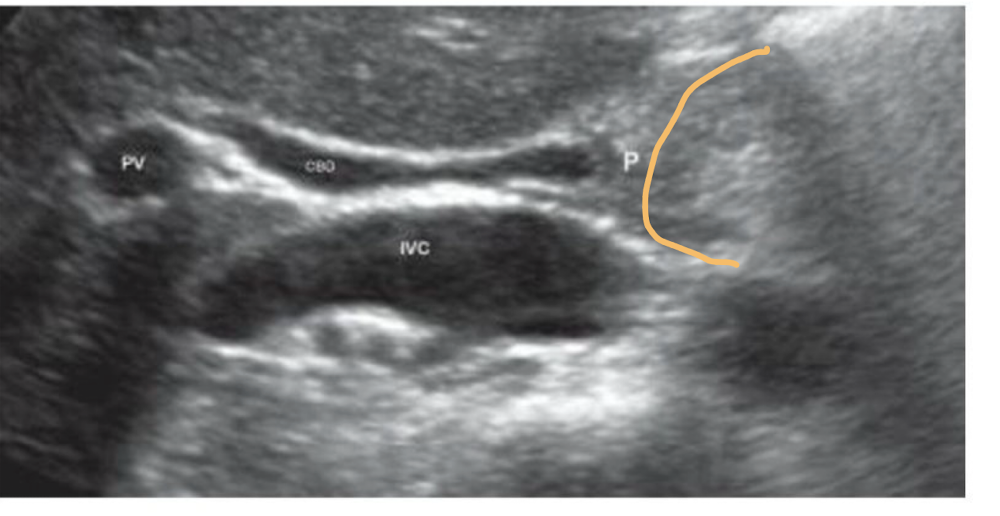

Which is shown in this image?

a longitudinal view of the CBD entering the pancreatic head. Pancreatic head outlined in orange